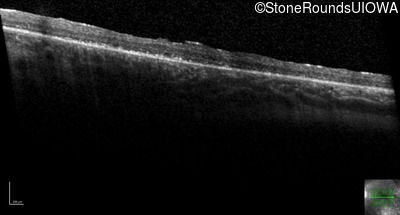

Optical Coherence Tomography - Right - 20/50

Exemplar / OCT Stack

OCT Stack